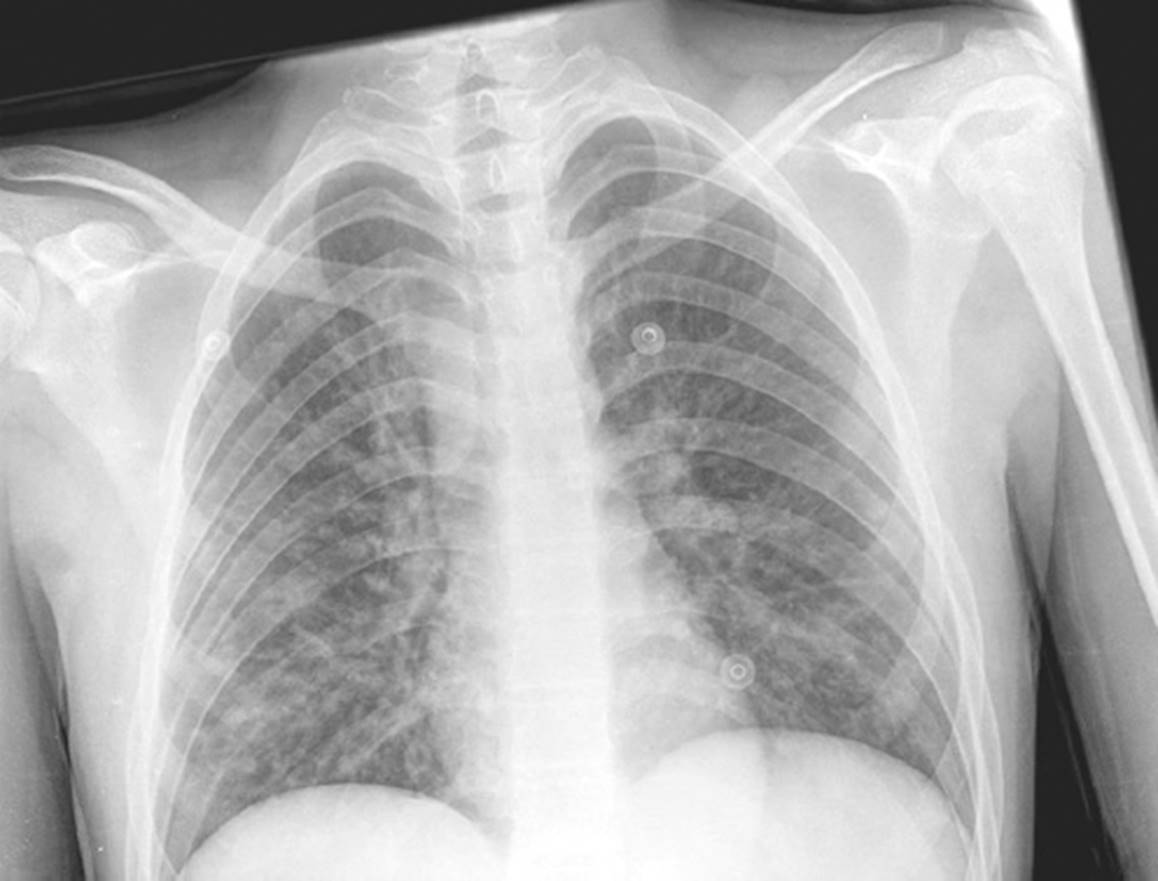

El aspirado endotraqueal mostró desarrollo de biota habitual y hemocultivos sin desarrollo bacteriano. En la radiografía de tórax se observó infiltrado intersticial difuso bilateral (Fig. 1). Al sexto día de internamiento se dio de alta por mejoría.

Varón de 15 años de edad (cepa 2351) con diagnóstico de linfoma de Hodgkin variedad esclerosis nodular en estadio IIB primario cervical-mediastinal con recaída temprana supradiafragmática e infradiafragmática en el segundo ciclo posrecaída. Recibió un primer ciclo con ifosfamida, vinblastina, citarabina y brentuximab; el segundo ciclo, con vinorelbina, ifosfamida y citarabina. Acudió después por tos y dificultad respiratoria de un día de evolución. En la exploración física se observaron adenopatías submandibulares bilaterales, móviles y no dolorosas, tórax con movimientos de amplexión y amplexación disminuidos, tiros intercostales bajos, retracción xifoidea, campos pulmonares hipoventilados, sibilancias basales y estertores. Su temperatura era de 39 °C, la frecuencia cardiaca de 159 latidos/min, la frecuencia respiratoria de 19/min, la saturación del 88%, la presión arterial de 102/68 mmHg, y los pulsos eran débiles. Los resultados de sus exámenes de laboratorio fueron: Hb 14.3 g/dl, Hto 42%, leucocitos 3,500/µl, neutrófilos 51%, neutrófilos totales 1,785, linfocitos 20%, monocitos 23%, eosinófilos 5%, basófilos 1%, plaquetas 210,000/µl, proteína C reactiva 2.48 mg/dl y procalcitonina < 0.10 ng/ml. Acidosis respiratoria compensada con lactato de 1.1 mmol/l. La radiografía de tórax mostró infiltrado con patrón mixto, difuso bilateral, sin evidencia de consolidación (Fig. 3). A su ingreso se le administraron dos cargas con cristaloides a dosis de 20 ml/kg. El paciente recibió tratamiento con cefepima (7 días) y amikacina (3 días), además de metilprednisolona intravenosa y micronebulizaciones con salbutamol y bromuro de ipratropio. Requirió presión positiva continua en las vías respiratorias (17 horas); posteriormente, mascarilla facial con reservorio a razón de 10 l/min y después aporte de O2 con puntas nasales a 1 l/min. Esto permitió lograr una saturación mayor del 90%. El tiempo de estancia hospitalaria fue de 9 días. El diagnóstico fue de neumonía adquirida en la comunidad por EV. El paciente fue dado de alta con puntas nasales a 1 l/min. La secuencia del genoma del EV-D68 obtenido fue incluida en la base de datos GenBank bajo el número KT825142.